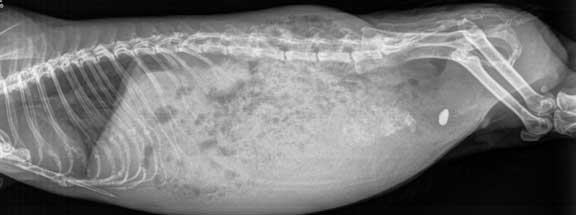

Radiology (X-Ray)

We might even take a pre-surgical radiograph to make sure we do not miss something on the inside. Small critters and the more exotic critters are masters at hiding illness, and there can be a problem brewing on the inside that the owner does not notice or is not apparent on a physical exam.

X-ray of a guinea pig with a bladder stone.

This is what happened in this case. Do you see the small white bladder stone on the right side of this radiograph? If you want to learn more about bladder stones in guinea pigs, and see how we surgical remove them, click here.